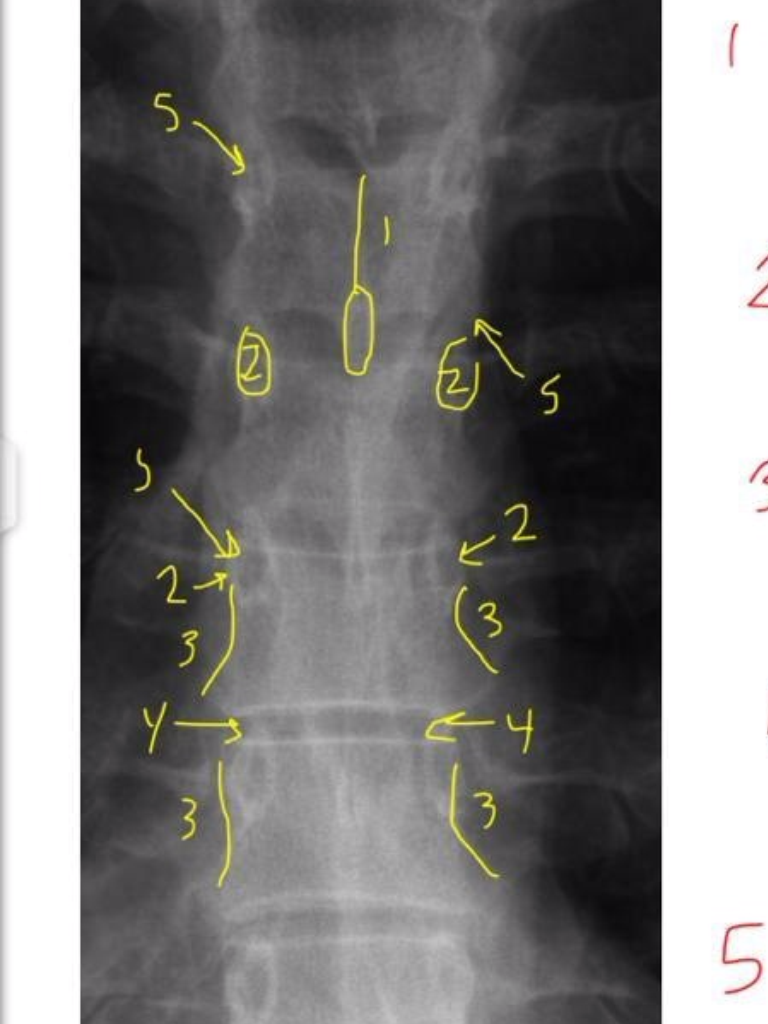

14

1

Occipital Condyle

(anterior/posterior)

15

2

Anterior Tubercle C1

16

3

Posterior Arch C1

17

4

Odontoid Process C2

18

5

Atlanto-Dental Interspace